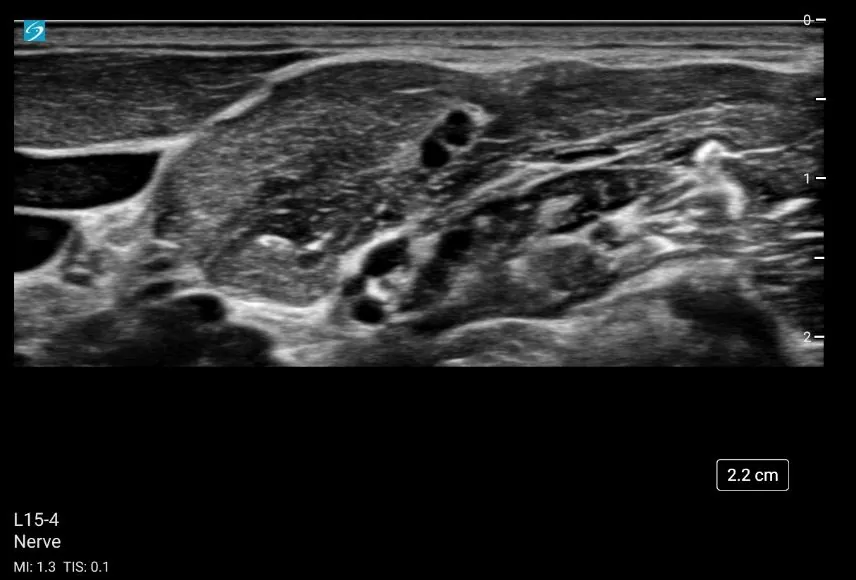

SonoSite ZX ir jaunākās paaudzes portatīvā ultraskaņas sistēma neatliekamajai medicīnai un reģionālajai anestezioloģijai. Tā novatoriskais raksturs nodrošina raitu darbplūsmu. Uzlabotās attēlveidošanas tehnoloģijas SonoADAPT™, SonoHD2™, ColorHD™, DirectClear tehnoloģija, Advanced Needle Visualization ļauj ievērojami uzlabot veiktspēju. Sistēmu var novietot uz statīva vai izmantot kā atsevišķu. SonoSite ultraskaņas sistēma un zondes ir triecienizturīgi un iztur kritienu no 90cm augstuma.